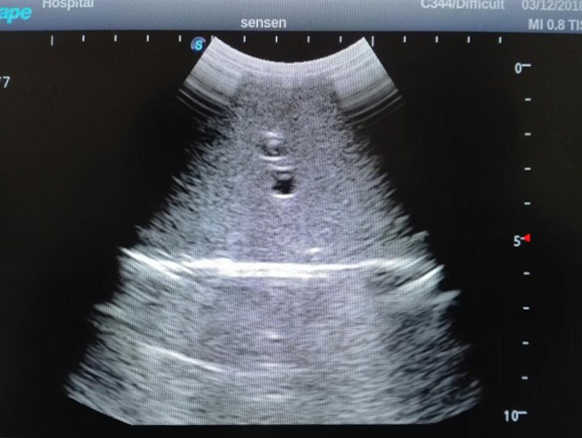

2)  High quality ultrasound image with clear structures like gallbladder, liver, intestines, arteries and veins etc.

4)  ltrasound gallbladder pathologies like cholecystitis, gallstone and polypoid degeneration